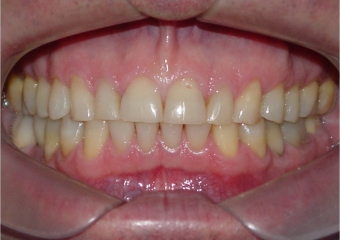

Mordida, após 2 anos da cirurgia